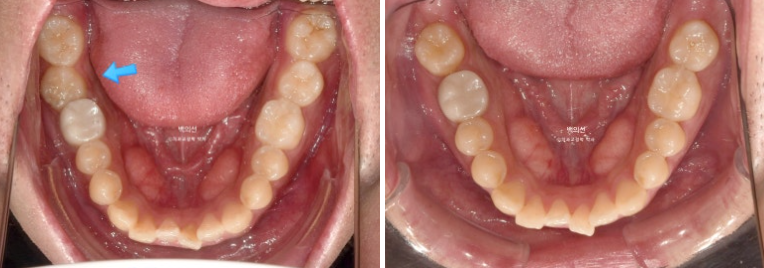

치료 전 후 비교해보겠습니다.

좌 치료 전 / 우 치료 후

24.01~25.05

총 치료기간은 1년 4개월이며 인비절라인으로 치료한 기간은 9개월 입니다.